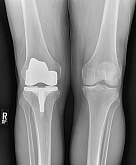

Еndoprosthesis of knee joint

In the late stages of arthrosis of the knee joint, accompanied by a pronounced restriction of the volume of movements, constant intense pain, deformity of the limb, the only way to recover is to replace the affected joint with an artificial joint - arthroplasty.

This method allows you to return the correct form of the limb, the full volume of movements in the joint, relieve the constant pain and crunch during movements and, as a result, significantly improve the patient's quality of life.

Below are presented X-ray photographs and photographs, illustrating the amount of motion in the affected joint before and after surgery.